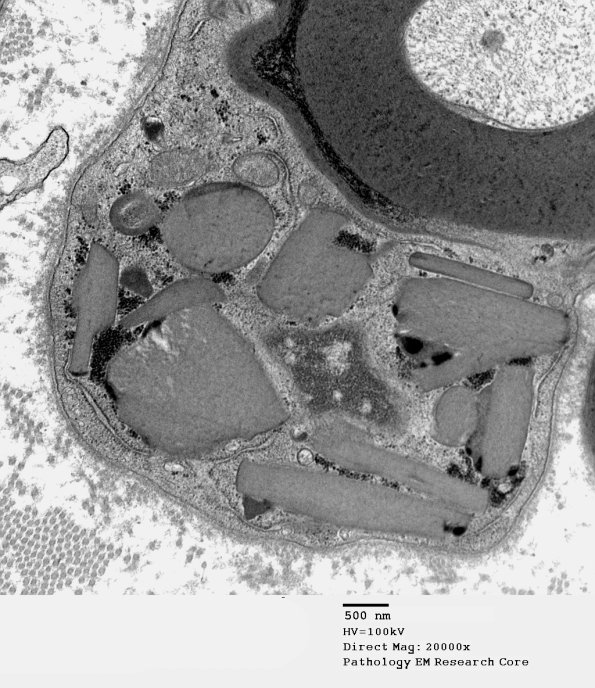

4B2 PG (Case 4) EM 124 - Copy

Higher magnification of image #4B1. (electron micrograph)